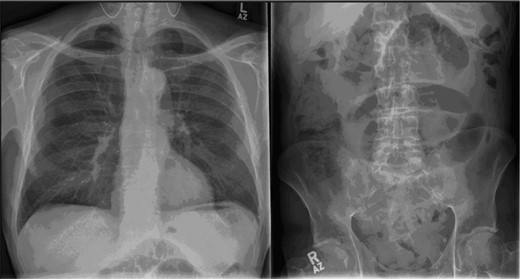

His blood on admission showed a raised white cell count of 12.5 × 103 cells/ml (with neutrophilia) and a C-reactive protein of 14.0 mg/l. His alanine transaminase was mildly raised at 79 U/l; however, his remaining liver and renal function tests were normal. His abdominal X-ray showed dilated loops of small bowel but no evidence of large bowel dilatation (Fig. 1). A provisional diagnosis of small bowel obstruction was made and a computerised tomography (CT) scan of the abdomen and pelvis was ordered. The CT showed multiple dilated loops of small bowel but no focus of obstruction (Fig. 2a). The gallbladder wall was thickened and oedematous and there was also evidence of gas within its lumen. Air was seen under the left lobe of the liver, suggestive of a bowel perforation. Furthermore, in Fig. 2b, the second part of the duodenum appears to be adherent and in communication to the gallbladder. Putting all these findings together, the radiologist felt that there was acute cholecystitis leading to a duodenal perforation and paralytic ileus.

Plain film of the chest and abdomen: the chest X-ray shows features suggestive of air under the diaphragm, while the abdominal film shows dilated loops of small and large bowel with air in the rectum, highly suggestive of ileus.